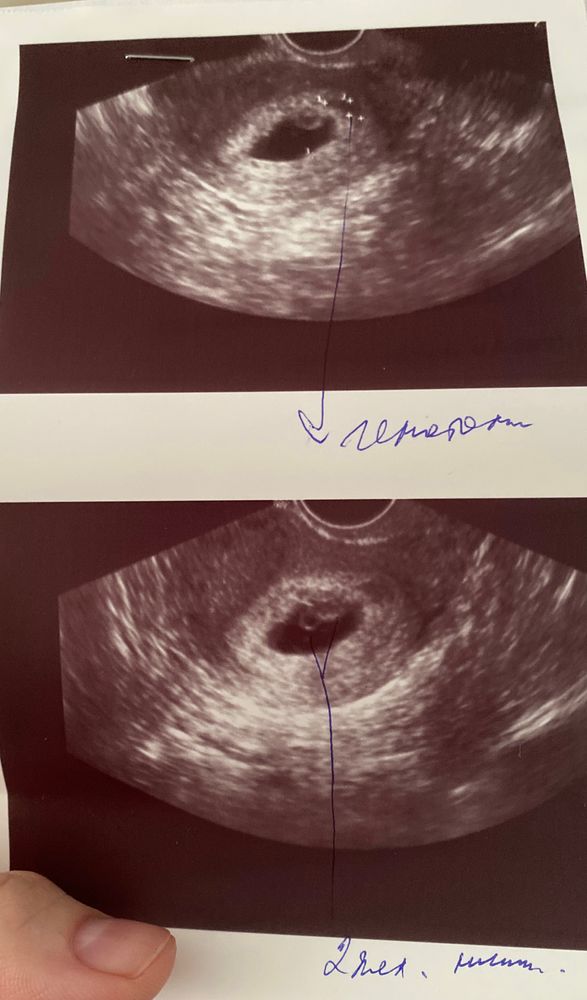

Опытные мамочки, подскажите, похоже ли это на многоплодную беременность?

На повторном узи (6 недель 4 дня) обнаружили 2 желточных мешочка. Эмбрион с сердцебиением нашли пока один только. Врач долго смотрела и сомневалась, желточный ли мешочек это или начала развиваться плацента. И вообще реально ли плаценту на узи спутать с желточным мешочком? Или может быть просто 2 желточных мешка, но один эмбрион?

С младшим сыном первое узи в 7.6 недель. На мониторе хорошо было видно 2 жм, 1 эмбрион сб+. Форма плодного яйца не овальная была, а измененная. По контрольному узи через 2 недели и намека на двойню не было. Вам сейчас только ждать и узи попозже переделать.